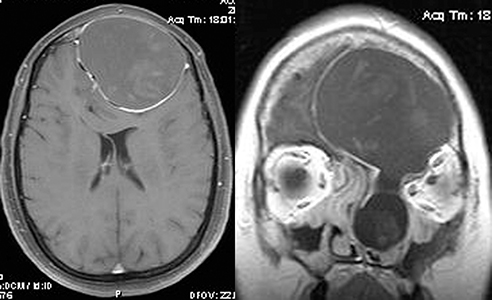

Dermoid and epidermoid cysts: Manifest clinically from birth to young adulthood and enlarge slowly. Preseptal dermoid cysts may become symptomatic in childhood and are most commonly found in the temporal upper eyelid or brow, and less often in the medial upper eyelid. The palpable, smooth mass may be mobile or fixed to the periosteum. Posterior dermoids typically become symptomatic in adulthood and may cause proptosis or globe displacement. Dermoid cyst rupture may mimic orbital cellulitis. The B-scan US, when used, reveals a cystic lesion with good transmission of echoes. Because of the cystic configuration and specific signal properties, CT and MRI are usually diagnostic. See 14.3, Magnetic Resonance Imaging.

Venolymphatic malformation (lymphangioma): Usually seen in the first two decades of life with a slowly progressive course but may abruptly worsen if the tumor spontaneously bleeds. Proptosis may be intermittent and exacerbated by upper respiratory tract infections. Lymphangioma may present as an atraumatic eyelid ecchymosis. Concomitant conjunctival, eyelid, or oropharyngeal lymphangiomas may be noted (a conjunctival lesion appears as a multicystic mass). MRI is often diagnostic. The B-scan US, when used, often reveals cystic spaces. See Figure 7.4.1.2.